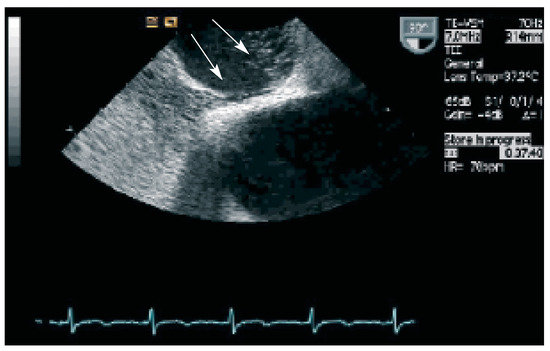

Investigating a Continuous Heart Murmur

by C. Roethlisberger and M. Braunschweig

Cardiovasc. Med. 2006, 9(1), 39; https://doi.org/10.4414/cvm.2006.01147 - 27 Jan 2006

A 42-year-old male with atypical chest pain was investigated for a 2/6 continuous murmur at the apex of the heart [...] Full article